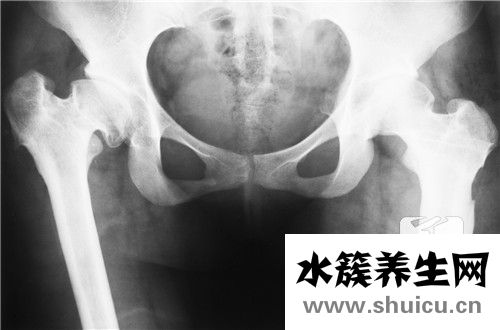

雙側骶髂關節(jié)炎是遺傳病。年齡越大越容易發(fā)展,男性患者總數(shù)遠遠高于女性患者。疾病的原因尚未確定。大部分患者臀部有疼痛,這種疼痛的抗壓強度比較高。如果生病了,可以考慮熱敷或者吃藥緩解。其次,如果比較嚴重,需要考慮醫(yī)院。醫(yī)生看了都有可能吃藥,針灸或者中醫(yī)按摩。

骶髂關節(jié)炎是關節(jié)炎中的骨關節(jié)炎的一種支系。大部分的骶髂關節(jié)炎并并不是獨立的一個病癥,只是由別的病癥造成的,如很多強直性脊椎炎炎的病人在病發(fā)前期主要表現(xiàn)為骶髂關節(jié)炎,因此 確診出骶髂關節(jié)炎還是不足的,應進一步查驗是哪種原因造成的。

雙側骶髂關節(jié)炎關鍵的臨床癥狀主要表現(xiàn)為骶髂關節(jié)位置的疼痛病癥,尤其是在疲勞或是著涼的狀況下,疼痛會更為強烈,比較嚴重的可能會影響到一切正常活動。這就是雙側骶髂關節(jié)炎的臨床表現(xiàn)。